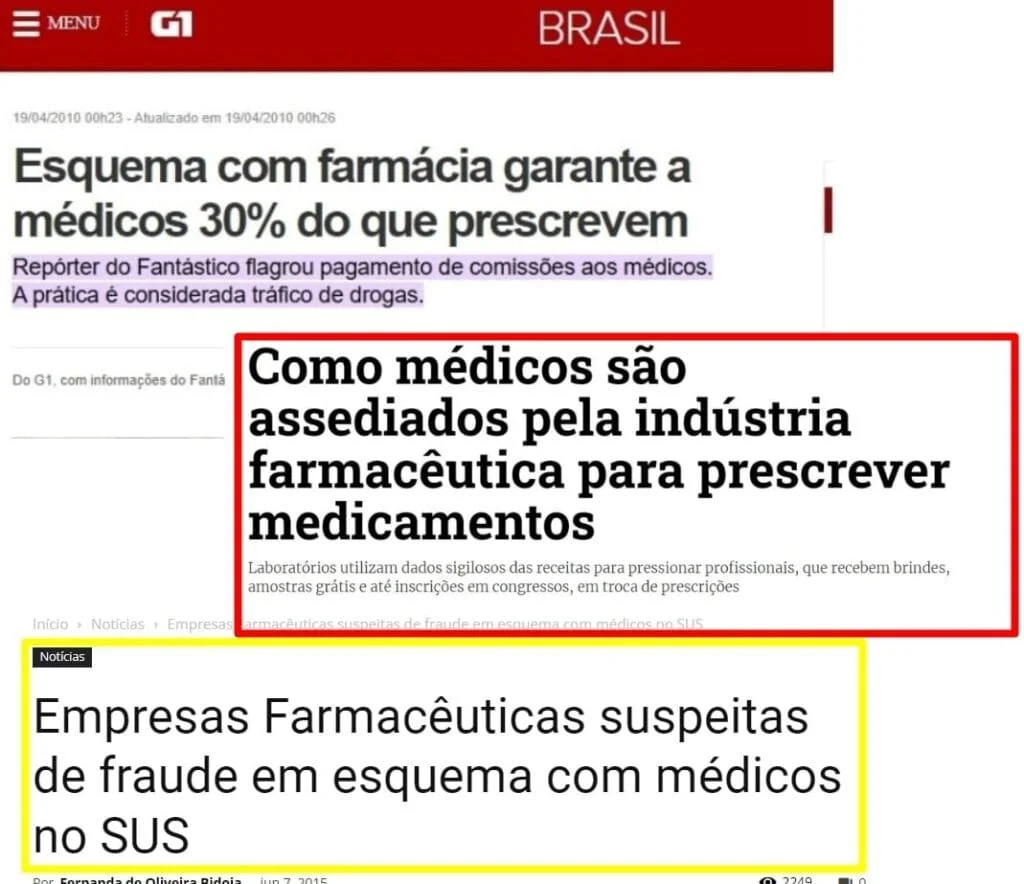

Os pacientes geralmente não sabem quais consequências os aguardam após o uso contínuo desse tipo de medicamento, e os médicos não acham necessário falar sobre o assunto, afinal, eles estão lucrando com isso..

Tratar o diabetes com medicamentos sintéticos agressivos é um crime! E há diversas matérias que comprovam como a indústria farmacêutica se beneficia dessa dependência.

Os médicos dizem que esses sintomas são do diabetes, mas, na verdade, são causados pela insulina! Mais exatamente, pela metformina, que faz o corpo produzir hormônios em níveis muito acima do normal.